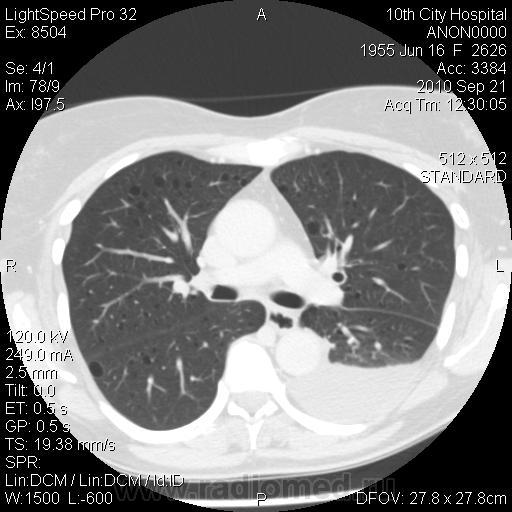

Немного предыстории: женщина поступила в плановое хирургическое отделение, по поводу кистозного образования в проекции головки ПЖ. (месяц назад лечилась по поводу острого панкреатита в другой больнице). В настоящее время на УЗИ - киста в области головки ПЖ. Мы сделали КТ - типичная карина псевдокисты в области головки. Но меня заинтересовали легкие. Из анамнеза узнал, что с 2004 года у пациентки постоянные рецидивирующие хилотораксы (лечилась во множестве больниц, диагноз не установлен). Вообщим сделали вчера КТ ОГК - что и выставляю.

Прошу прощения, сразу не заметил - выложенная реконструкция сделана на ВЫДОХЕ.

В области бифуркации лёгочного ствола киста? средостения. Гидроторакс слева. Что я пропустила?

Да нет, я решил, что это лимфангиолейомиоматоз...

Больше в нижних отделах эмфизаматозные буллы различных размеров, междолевые плвра уплотнены, слева в плевральной полости выпот.

А мне кажется это не просто буллы... Как и писал выше - склоняюсь к LAM